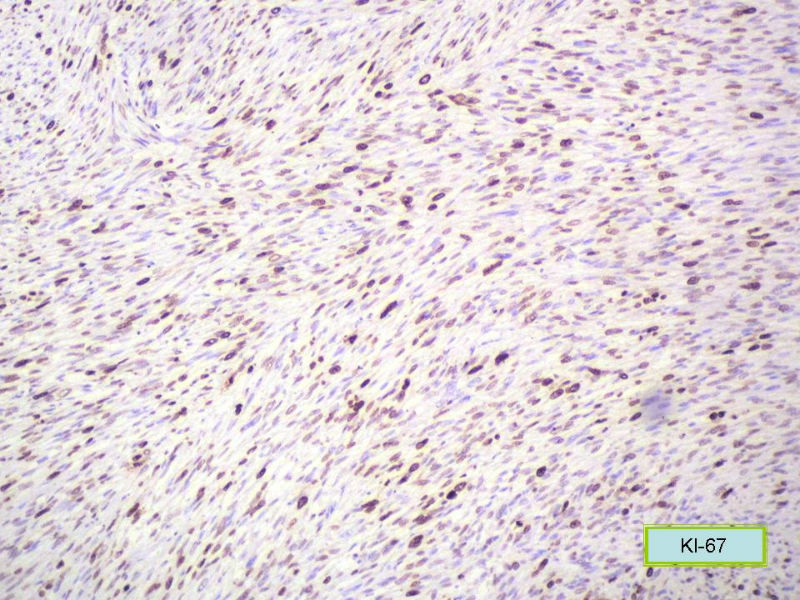

女,71岁,胸闷2月余,CT提示纵膈占位。手术见左肺与胸膜之间有一肿块,与周围粘连,手术切除。肉眼,肿块7X5X3厘米,边界较清楚,切面灰白灰红,质韧。

镜检:核分裂5</10HP

此例我们诊断为平滑肌肉瘤,因为很少见,请各位老师讨论!

形态学和免疫组化标记符合平滑肌肉瘤,但要标记Myogenin等鉴别横纹肌肉瘤,标记D2-40、Calretinin等鉴别肉瘤样间皮瘤。